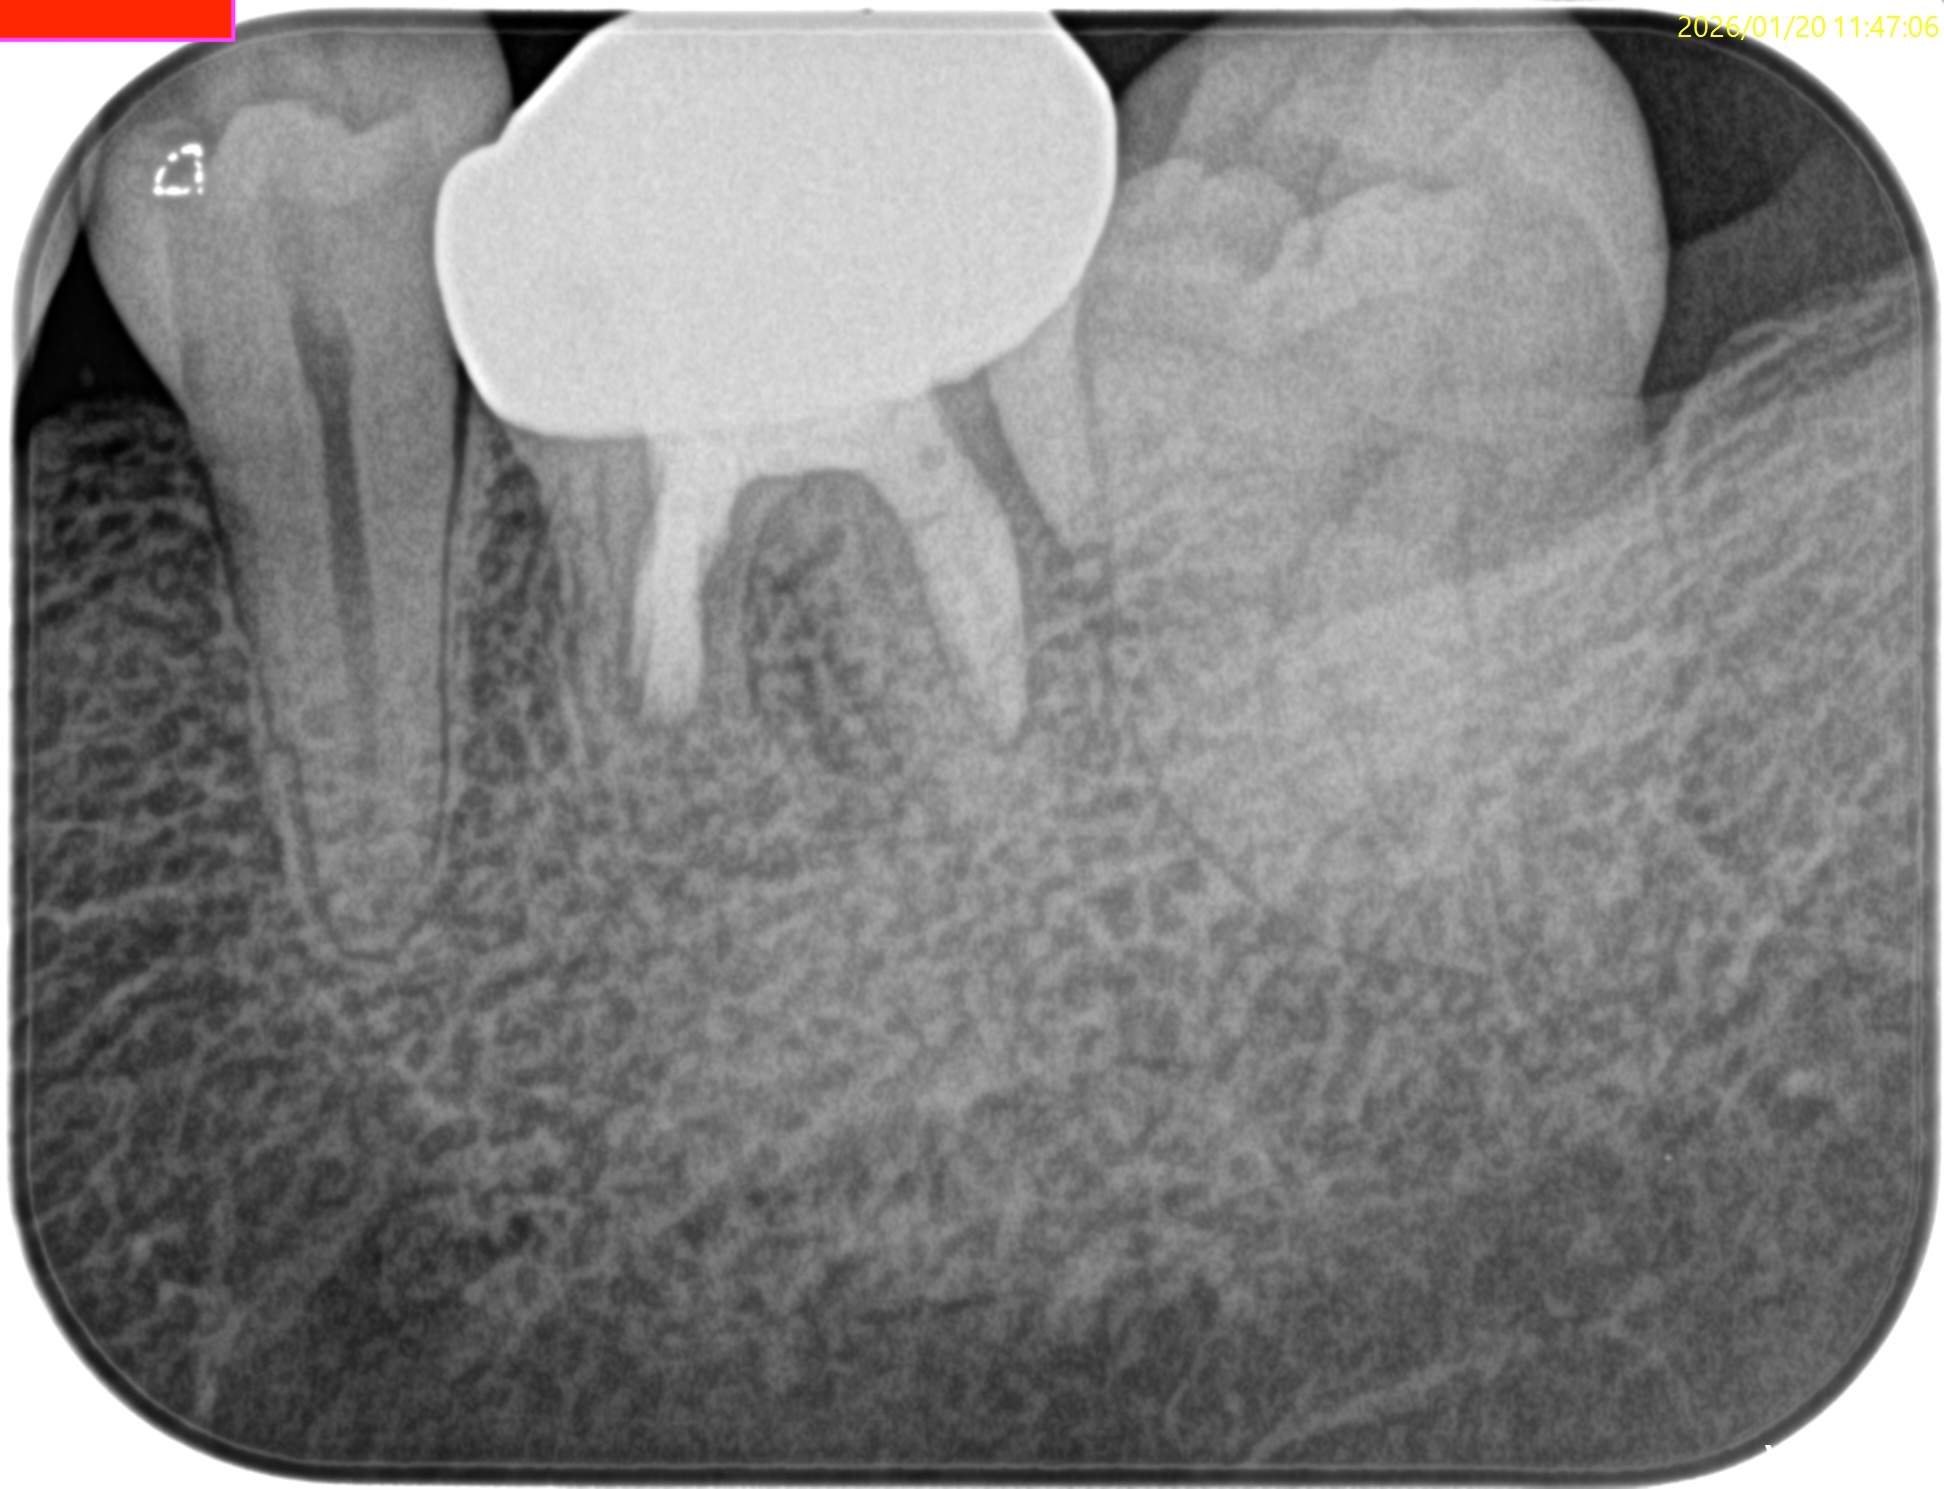

術後にPA, CBCTを撮影した。

問題はないだろう。

Post-op 1yr Endo test(2026.1.20)

術後の骨欠損は完治した。